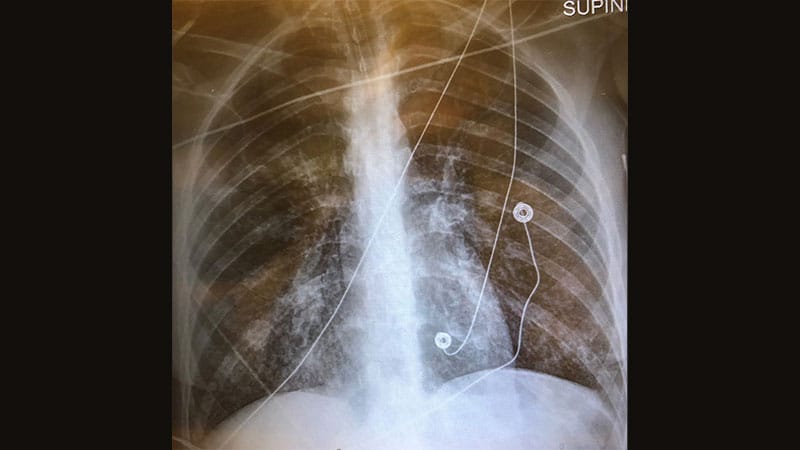

Cardiovascular Risk Reduction: Protecting the Aging Heart: More Than Risk Factors

Cardiovascular Risk Reduction: Protecting the Aging Heart: CVD Prevention in Type 2 Diabetes -